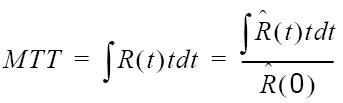

| CBF |  |  |

| MTT |  |  |

Mean Transit Time

Mean Transit Time (MTT) measures the length of time a certain volume of blood spends in the cerebral capillary circulation.